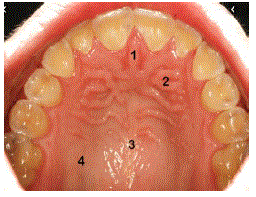

Observe a imagem a seguir e as afirmações de acordo com a nomenclatura anatômica indicada pela numeração do palato duro:

I - 1: Rafe palatina.

II - 2: Pregas palatinas transversas.

III - 3: Prega franjada.

É CORRETO o que se afirma em: